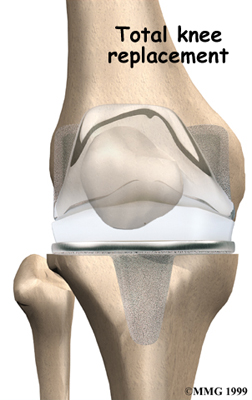

Artificial Knee Replacement

An artificial knee replacement is the ultimate solution for advanced knee OA.

Surgeons prefer not to put a new knee joint in patients younger than 60. This is because younger patients are generally more active and might put too much stress on the joint, causing it to loosen or even crack. A revision surgery to replace a damaged prosthesis is harder to do, has more possible complications, and is usually less successful than a first-time joint replacement surgery.

Related Document: FYZICAL Madison West's Guide to Artificial Joint Replacement of the Knee